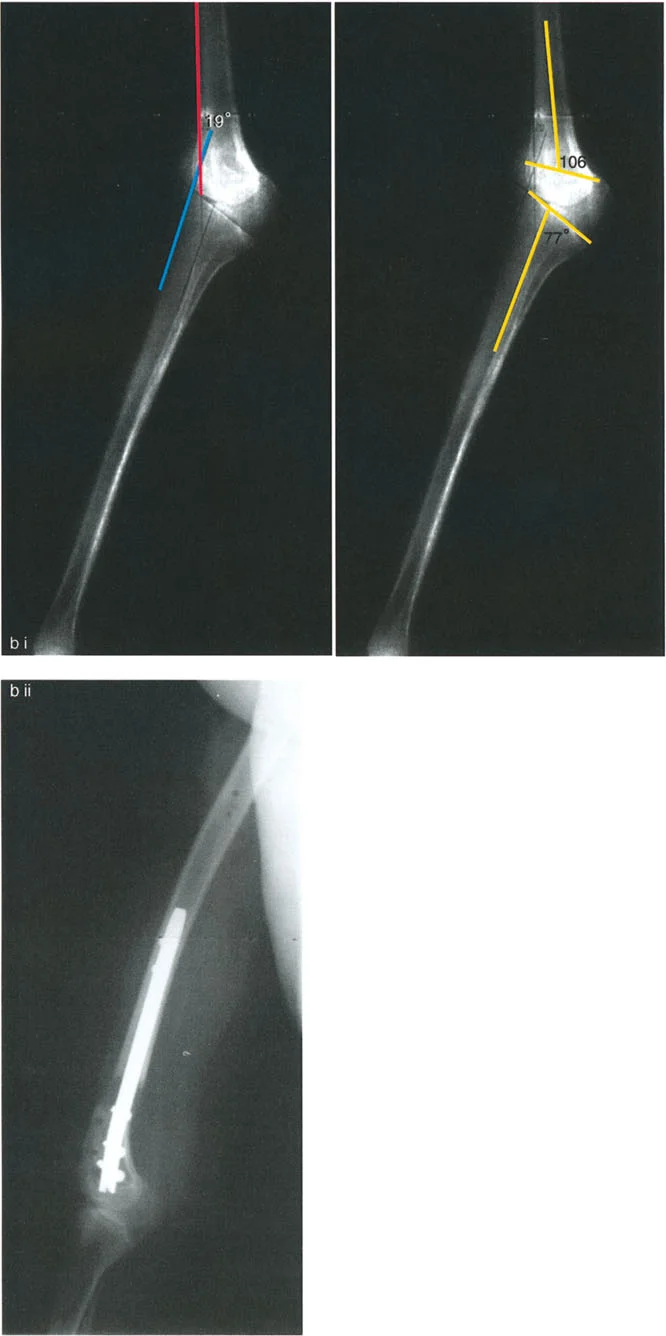

- تقييم مدى الحركة: يتم قياس مدى حركة الركبة، بما في ذلك أقصى تمدد وأقصى انثناء. يتم تحديد درجة فرط التمدد (HE - Hyperextension) أو درجة تقلص الانثناء الثابت (FFD - Fixed Flexion Deformity).

زوايا القياس الهامة:

- زاوية الانحناء البعيدة للفخذ (PDFA - Posterior Distal Femoral Angle): تقيس زاوية الجزء السفلي من عظم الفخذ. القيمة الطبيعية حوالي 84 درجة. الزيادة في هذه الزاوية (أكثر من 84 درجة) تشير إلى ارتداد فخذي.

- زاوية الانحناء القريبة للظنبوب (PPTA - Proximal Posterior Tibial Angle): تقيس زاوية الجزء العلوي من عظم الساق. القيمة الطبيعية حوالي 80 درجة. الزيادة في هذه الزاوية (أكثر من 80 درجة) تشير إلى ارتداد ظنبوبي.

- مركز دوران الزاوية (CORA - Center of Rotation of Angulation): يتم تحديد هذا النقطة على الأشعة السينية لتحديد مكان التشوه العظمي بدقة، وهو أمر بالغ الأهمية لتخطيط عملية قطع العظم.

- الركبة الارتدادية بسبب الارتداد الفخذي:

- إذا كانت درجة فرط التمدد (HE) تساوي درجة الارتداد الفخذي (PDFA > 84°)، فهذا يعني أن التشوه كله ناتج عن عظم الفخذ.

- في هذه الحالة، يكون مركز CORA في الجزء البعيد من عظم الفخذ.

- الركبة الارتدادية بسبب الارتداد الفخذي مع تقلص انثناء:

- إذا كان هناك ارتداد فخذي (PDFA > 84°) ولكن لا يوجد فرط تمدد سريري (HE = 0°)، فهذا يشير إلى وجود تقلص انثناء مصاحب يعوض التشوه العظمي.

- إذا كان فرط التمدد (HE) أقل من درجة الارتداد الفخذي، فهذا يعني وجود تقلص انثناء جزئي.

أ. قطع العظم الفخذي لتصحيح الارتداد الفخذي:

- متى يتم إجراؤها: عندما يكون التشوه الرئيسي في عظم الفخذ البعيد.

- الإجراء: يتم إجراء قطع للعظم (عادة قطع عظم انثناء) في الجزء البعيد من عظم الفخذ، عند مركز دوران الزاوية (CORA)، لإعادة محاذاة العظم.

- الهدف: تصحيح فرط تمدد الركبة واستعادة المحاذاة الطبيعية.

- مثال: لتصحيح ارتداد فخذي بمقدار 20 درجة، يتم إجراء قطع عظم انثناء فخذي بمقدار 20 درجة.